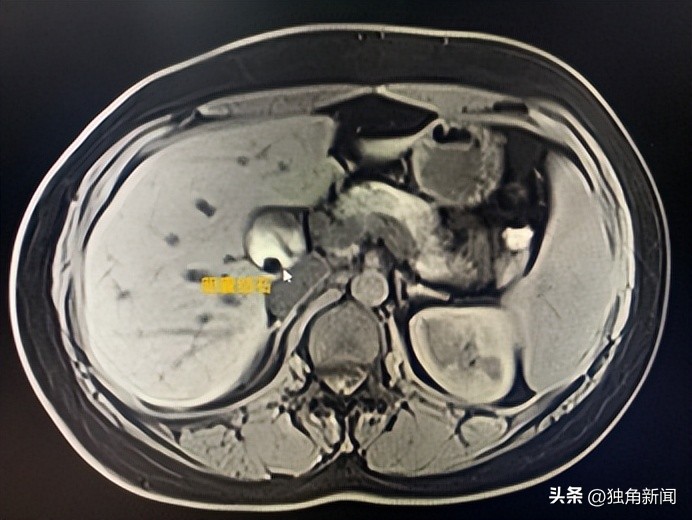

近日,34岁的刘女士因腹部疼痛到大连市第三人民医院急诊就诊,结合刘女士上腹部疼痛的症状、体征以及相关的化验检查,会诊医生普外二科闫龙超诊断其为胆囊结石、胆总管结石合并胆囊炎。

胆石症,是指胆道系统包括胆囊及胆管内发生结石的疾病,按发生部位分为胆囊结石和胆管结石。结石在胆囊内形成后,可刺激胆囊黏膜形成炎症,导致慢性胆囊炎或急性胆囊炎。

如果结石经胆囊管排入胆总管,形成胆总管结石,可引起梗阻性黄疸、急性化脓性胆管炎、急性胰腺炎等严重疾病,甚至危及生命。